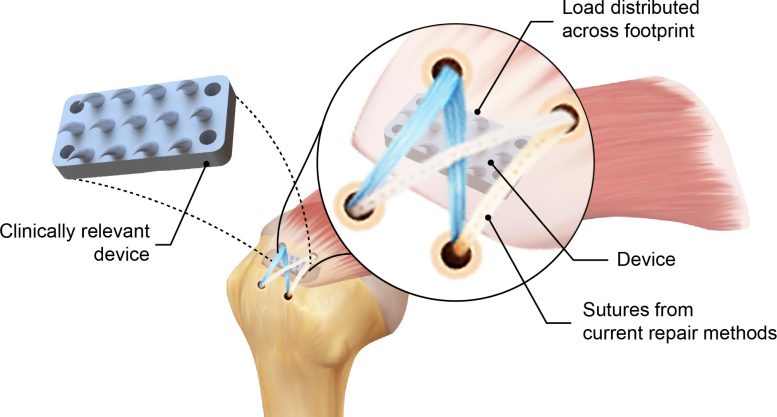

סכימה של ההתקן בהשראת שן הפיתון המוכנס בין גיד לעצם משפר משמעותית את תיקון השרוול המסובב הסטנדרטי. קרדיט: Iden Kurtaliaj/Columbia Engineering

הרעיון המקורי של הצוות היה להעתיק את הצורה של שיני פיתון, אבל הם הלכו הרבה יותר רחוק, תוך שימוש בסימולציות, הדפסת תלת מימד ו ex vivo ניסויים על גופות כדי לחקור את הקשר בין צורת השן ואחיזה לעומת מכניקת חיתוך. Kurtaliaj ייצר מגוון של עיצובי שיניים, אופטימיזציה של שיניים בודדות, מערכי שיניים, ולבסוף מערך שיניים ספציפי לשרוול מסובב.

התוצאה הסופית הייתה מכשיר ביומימטי, עשוי שרף ביו-תואם – מערך שיניים על גבי בסיס מעוקל – המסוגל לאחוז, לא לחתוך, גיד. השיניים קטנות יחסית – גובה של 3 מ"מ עבור שרוול מסתובב אנושי, בערך מחצית מהאורך של סיכות סטנדרטית – כך שהן לא יכנסו דרך הגיד. ניתן להתאים אישית את הבסיס באמצעות הדפסת תלת מימד כדי להתאים לעקמומיות הספציפית למטופל של ראש עצם הזרוע באתר החיבור לגיד הסופרספינאטוס (הגיד המסובב הנקרע לרוב).

"תכננו אותו במיוחד כך שהמנתחים לא יצטרכו לנטוש את הגישה הנוכחית שלהם – הם יכולים פשוט להוסיף את המכשיר ולהגביר את עוצמת התיקון שלהם", ציין קורטליאג'.